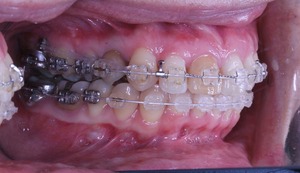

虫歯治療はきちんとされてますが、奥歯に全部銀歯の状態の歯があります。

当然、神経もない歯です。治療されたのはだいぶ前とのことでした。

それでは治療経過です

少し経過が進みました